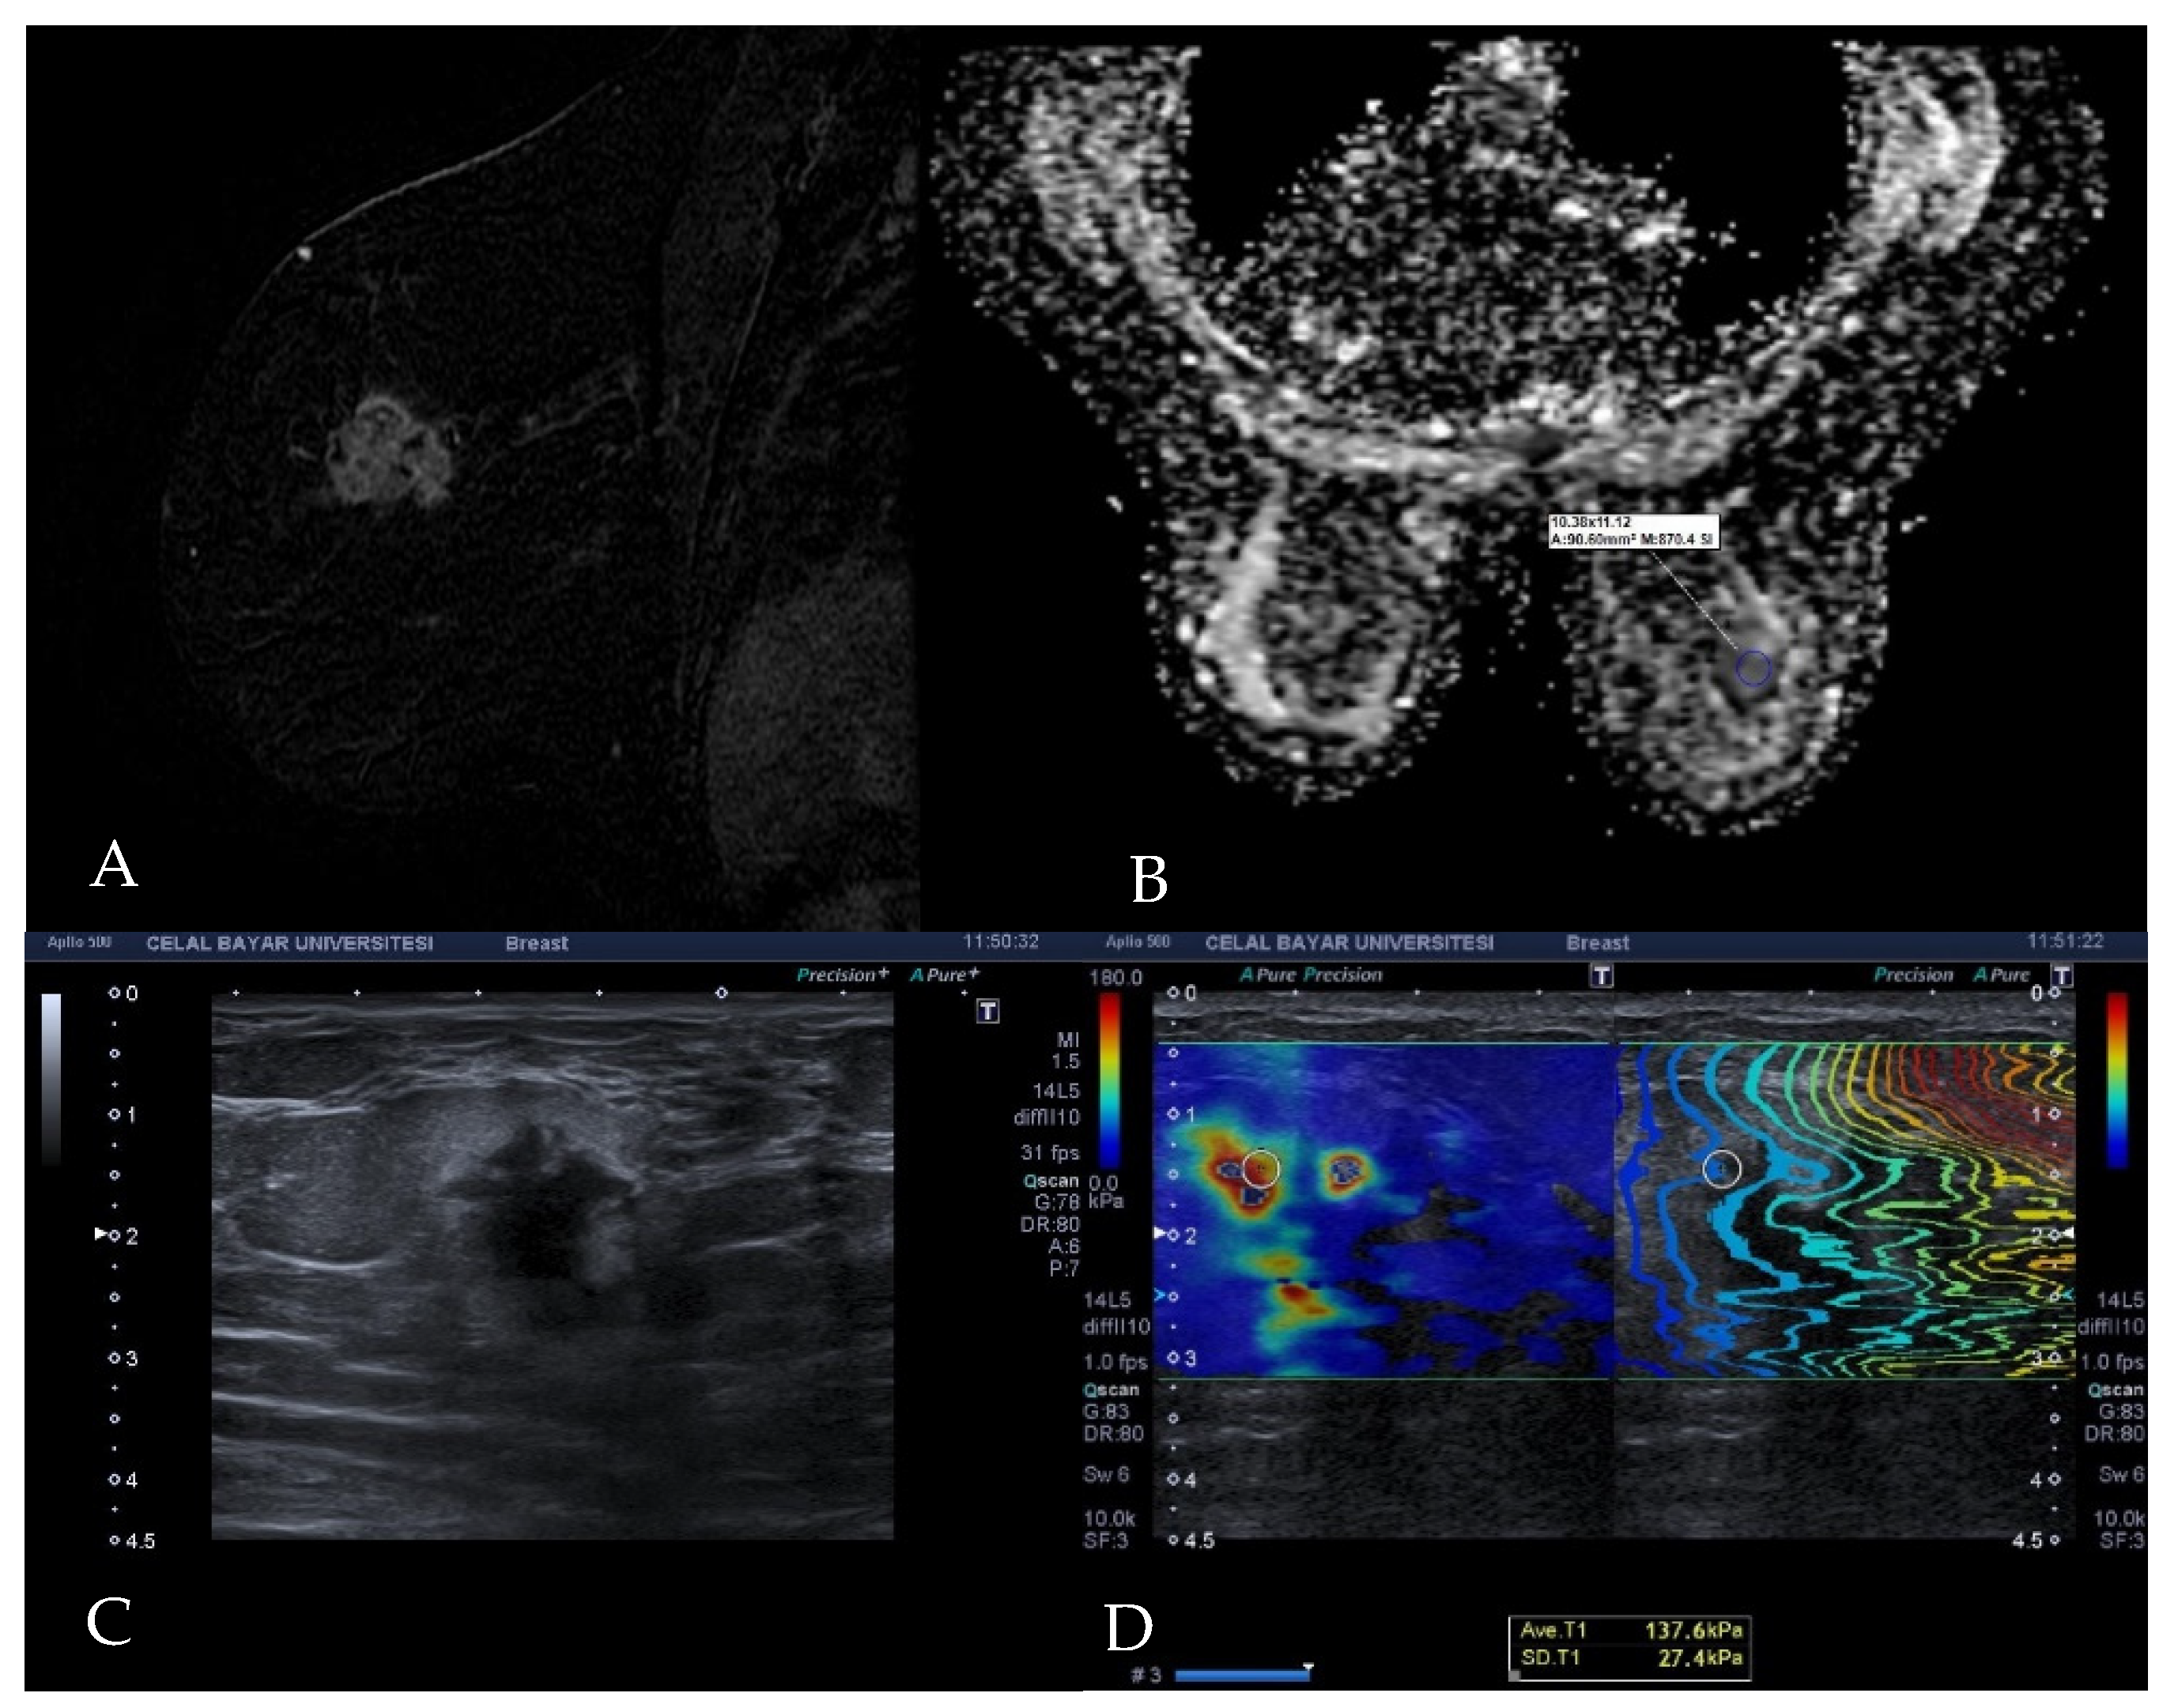

Figure 2. Images of invasive ductal carcinoma in a 36-year-old female patient. (A) Contrast-enhanced sagittal T1w image demonstrates a mass with irregular shape and contours and heterogeneous enhancement. (B) The lesion has a low signal on the ADC map with the value of 0.77 × 10−3 cm2/s. (C) B-mode ultrasonography shows a hypoechoic mass with angular margins. (D) Shear wave elastography reveals the mass is stiff with an elasticity value of 137.6 kPa.

A standard ROI (region of interest) was placed on areas with parallel contours on the propagation map at the stiffest part of the target lesion, as indicated by the color mapping, and thus the shear wave property of the breast cancer was quantified in KPa units (Figure 2). All images and measurements were recorded in the picture archive communication system (PACS).

2.3. Diffusion MRI Examination Technique